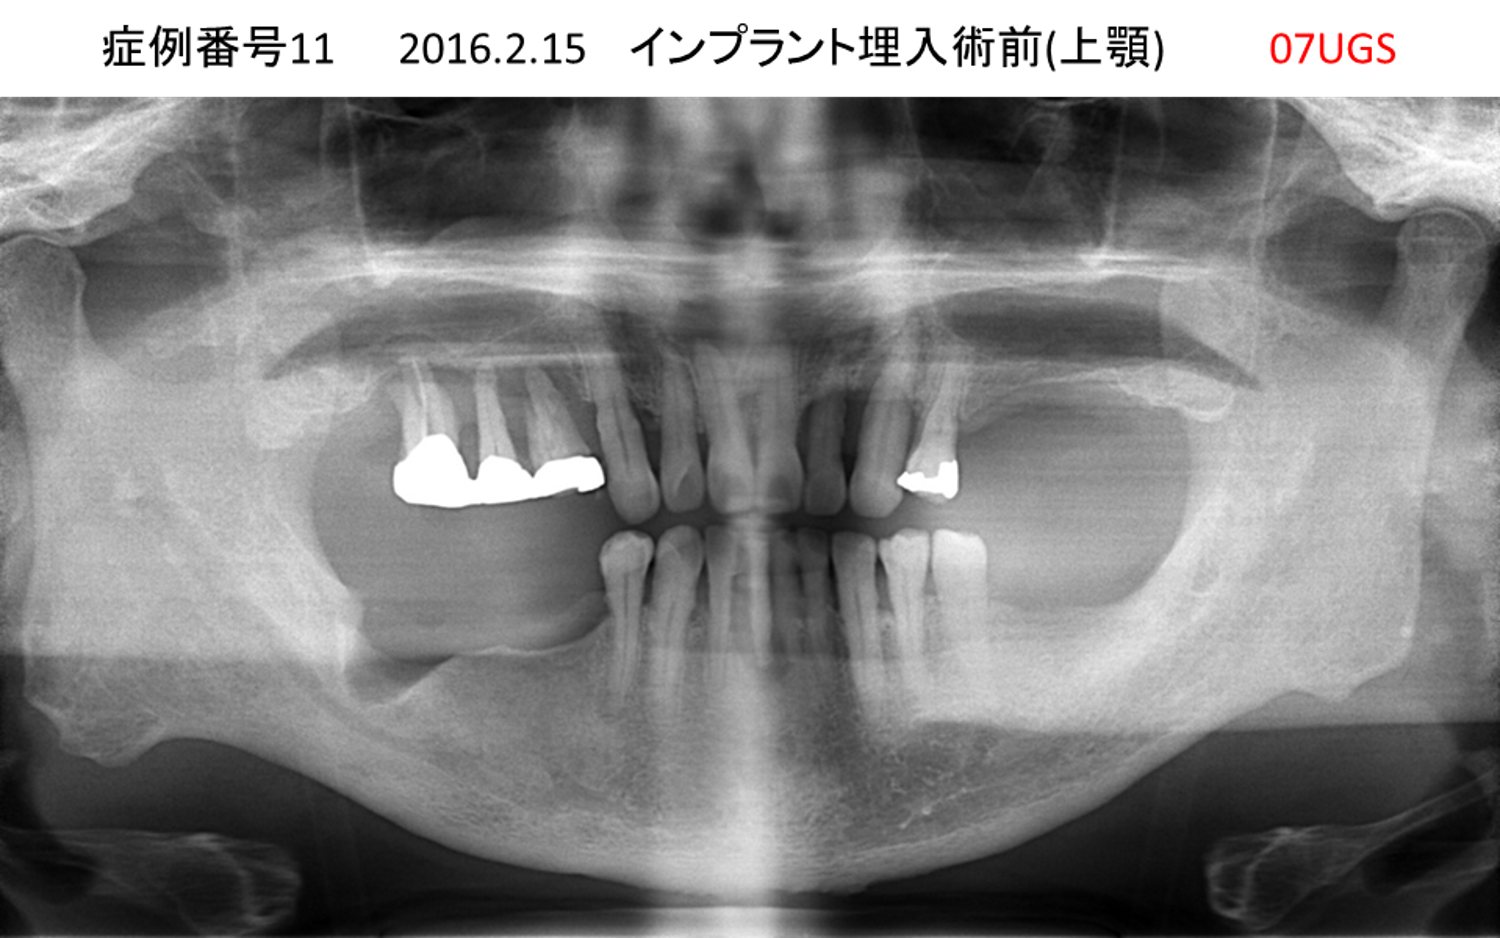

全く噛めない患者様のインプラント症例

| 治療名称 |

インプラントオーバーデンチャー |

| 治療費用 |

520万円+税 |

| 治療期間 |

6か月 |

| 患者さんの症状(主訴) |

全く噛めない。何とかしてほしい |

| 治療内容 |

サイナスリフト、インプラント、義歯作製(ロケーター) |

| 治療結果 |

好きなものが食べられるようになった。見栄えがとても良くなった。 |

| 治療の注意点(リスク/副作用) |

義歯が壊れた場合、インプラントが壊れた場合は再治療が必要 |